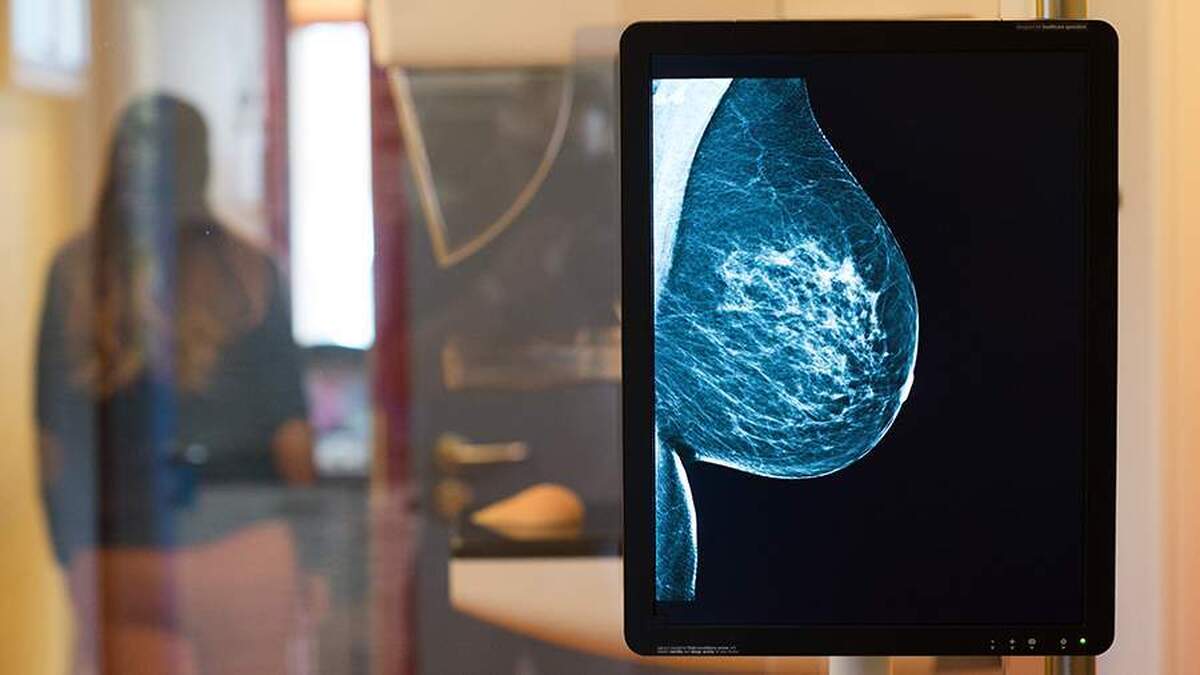

به گزارش مجله خبری نگار،اگرچه میانگین سنی زنان مبتلا به سرطان سینه در روسیه تقریباً ۶۱ سال است، اما تقریباً از هر ده مورد، یک مورد در بیماران زیر ۴۰ سال رخ می‌دهد. اولگا اولانکینا، متخصص زنان و زایمان و پزشک متخصص در آزمایشگاه هموتست، با ایزوستیا در مورد اینکه آیا امکان حفظ باروری پس از درمان وجود دارد، صحبت کرد.

ایجاد تومور بدخیم سینه در مراحل اولیه اغلب بدون علامت است. بنابراین، خودآزمایی و معاینات سالانه سینه بسیار مهم هستند. تشخیص زودهنگام، ملایم‌ترین درمان را ممکن می‌سازد که نه تنها به حفظ سلامت، بلکه به احتمال بارداری در آینده نیز کمک می‌کند.

«توصیه می‌شود حداقل ماهی یک بار خودتان سینه‌های خود را معاینه کنید. هنگام لمس، توجه به هرگونه توده در سینه‌ها و زیر بغل، تغییر در شکل سینه یا نوک سینه، ظاهر ترشحات (به خصوص خونی) و قرمزی پوست مهم است. در صورت بروز این علائم، باید با متخصص زنان مشورت کنید. پزشک معاینه را انجام داده و آزمایش‌های لازم را تجویز می‌کند. این متخصص توضیح می‌دهد: «برای نظارت منظم، به زنان زیر ۴۰ سال توصیه می‌شود سالانه سونوگرافی سینه و به زنان بالای ۴۰ سال توصیه می‌شود ماموگرافی انجام دهند.»